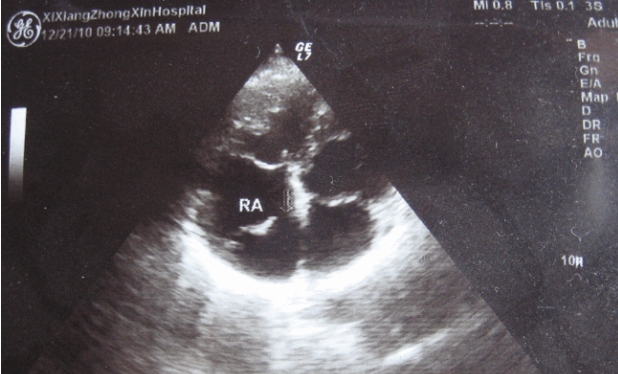

彩超是一种利用超声波进行无创检测的医疗技术,其原理是通过超声波在人体内部产生回声,然后利用电子学技术将这些回声转化为图像。通过颜色变化来反映不同组织或血流的速度和方向,从而帮助医生进行诊断。彩超其实并不是单纯的黑白图像,而是由各种灰度值构成的。在彩超中,不同的灰度值代表了不同的声强信号,也就是不同的回声强度,而这些回声强度的差异则反映了人体内部组织的密度、形态等特征。

那么为什么彩超不能直接输出彩色图像呢?这是因为彩色图像需要RGB三种颜色通道来表示,而彩超只有单色超声波发射器和接收器。为了实现彩色显示,必须对超声波信号进行频率分离和处理,即把超声信号分成许多不同的频率,然后通过计算得出不同频率的回声强度,并将其映射至RGB颜色空间中。

这也就是彩超中Color Doppler技术的实现原理,通过对超声波信号进行多普勒频移分析,即将回声信号中因血液流动而引起的频率变化(多普勒效应)提取出来,从而反映出血液的流速和流向,并将其在图像上以不同颜色的形式呈现出来。

值得注意的是,虽然彩超是一项非常先进的医疗技术,但它也有一些局限性。在检测深部组织或器官时,超声波信号会因经过不同的介质而发生衰减和散射,从而影响回声信号的质量和清晰度,导致图像不够准确。在肥胖或气体积聚的患者中,也容易出现影像窗口的限制,使得超声检查的效果大打折扣。不过彩超的技术原理实现也为广大医生提供了更加精确和可靠的诊断工具。